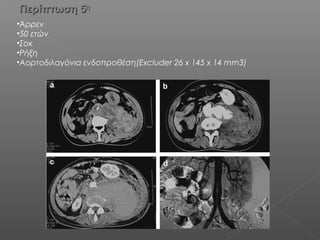

Περίπτωση 5Περίπτωση 5ηη

•Άρρεν

•50 ετών

•Σοκ

•Ρήξη

•Αορτοδιλαγόνια ενδοπροθέση(Excluder 26 x 145 x 14 mm3)